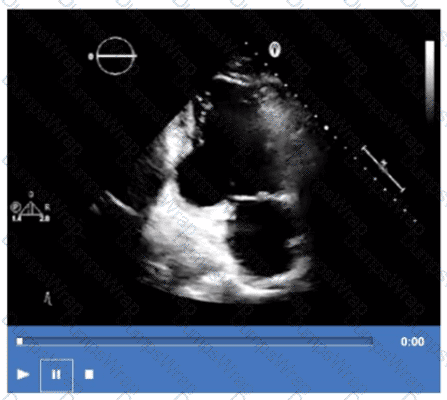

Which wall is indicated by the arrow on this video?

DExplanation:

Comprehensive and Detailed Explanation From Exact Extract:

The apical two-chamber echocardiographic view displays the inferolateral wall (also called posterior lateral). The arrow points to this inferolateral segment, which is located inferiorly and laterally in the left ventricle.

Anteroseptum and inferoseptum relate to the interventricular septum, while anterolateral is the anterior lateral wall, opposite the inferolateral wall. Correct regional wall motion assessment is essential for ischemic disease evaluation.

This identification and terminology are described in ASE stress echocardiography and chamber quantification guidelines【12:ASE Stress Echocardiography Guidelines†p.310-315】【16:Textbook of Clinical Echocardiography, 6e†p.380-385】.